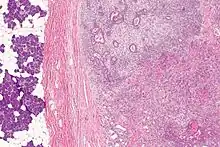

| Micrograph of a carcinoma ex pleomorphic adenoma. The carcinoma component is on the lower right of the image. Benign parotid gland is seen at the left and pleomorphic adenoma is seen at the upper right. H&E stain. | |

Carcinoma ex pleomorphic adenoma (ca ex PA) is a type of cancer typically found in the parotid gland. It arises from the benign tumour pleomorphic adenoma.

Carcinoma ex pleomorphic adenoma is diagnosed by examining it under the microscope with consideration of the individual history.